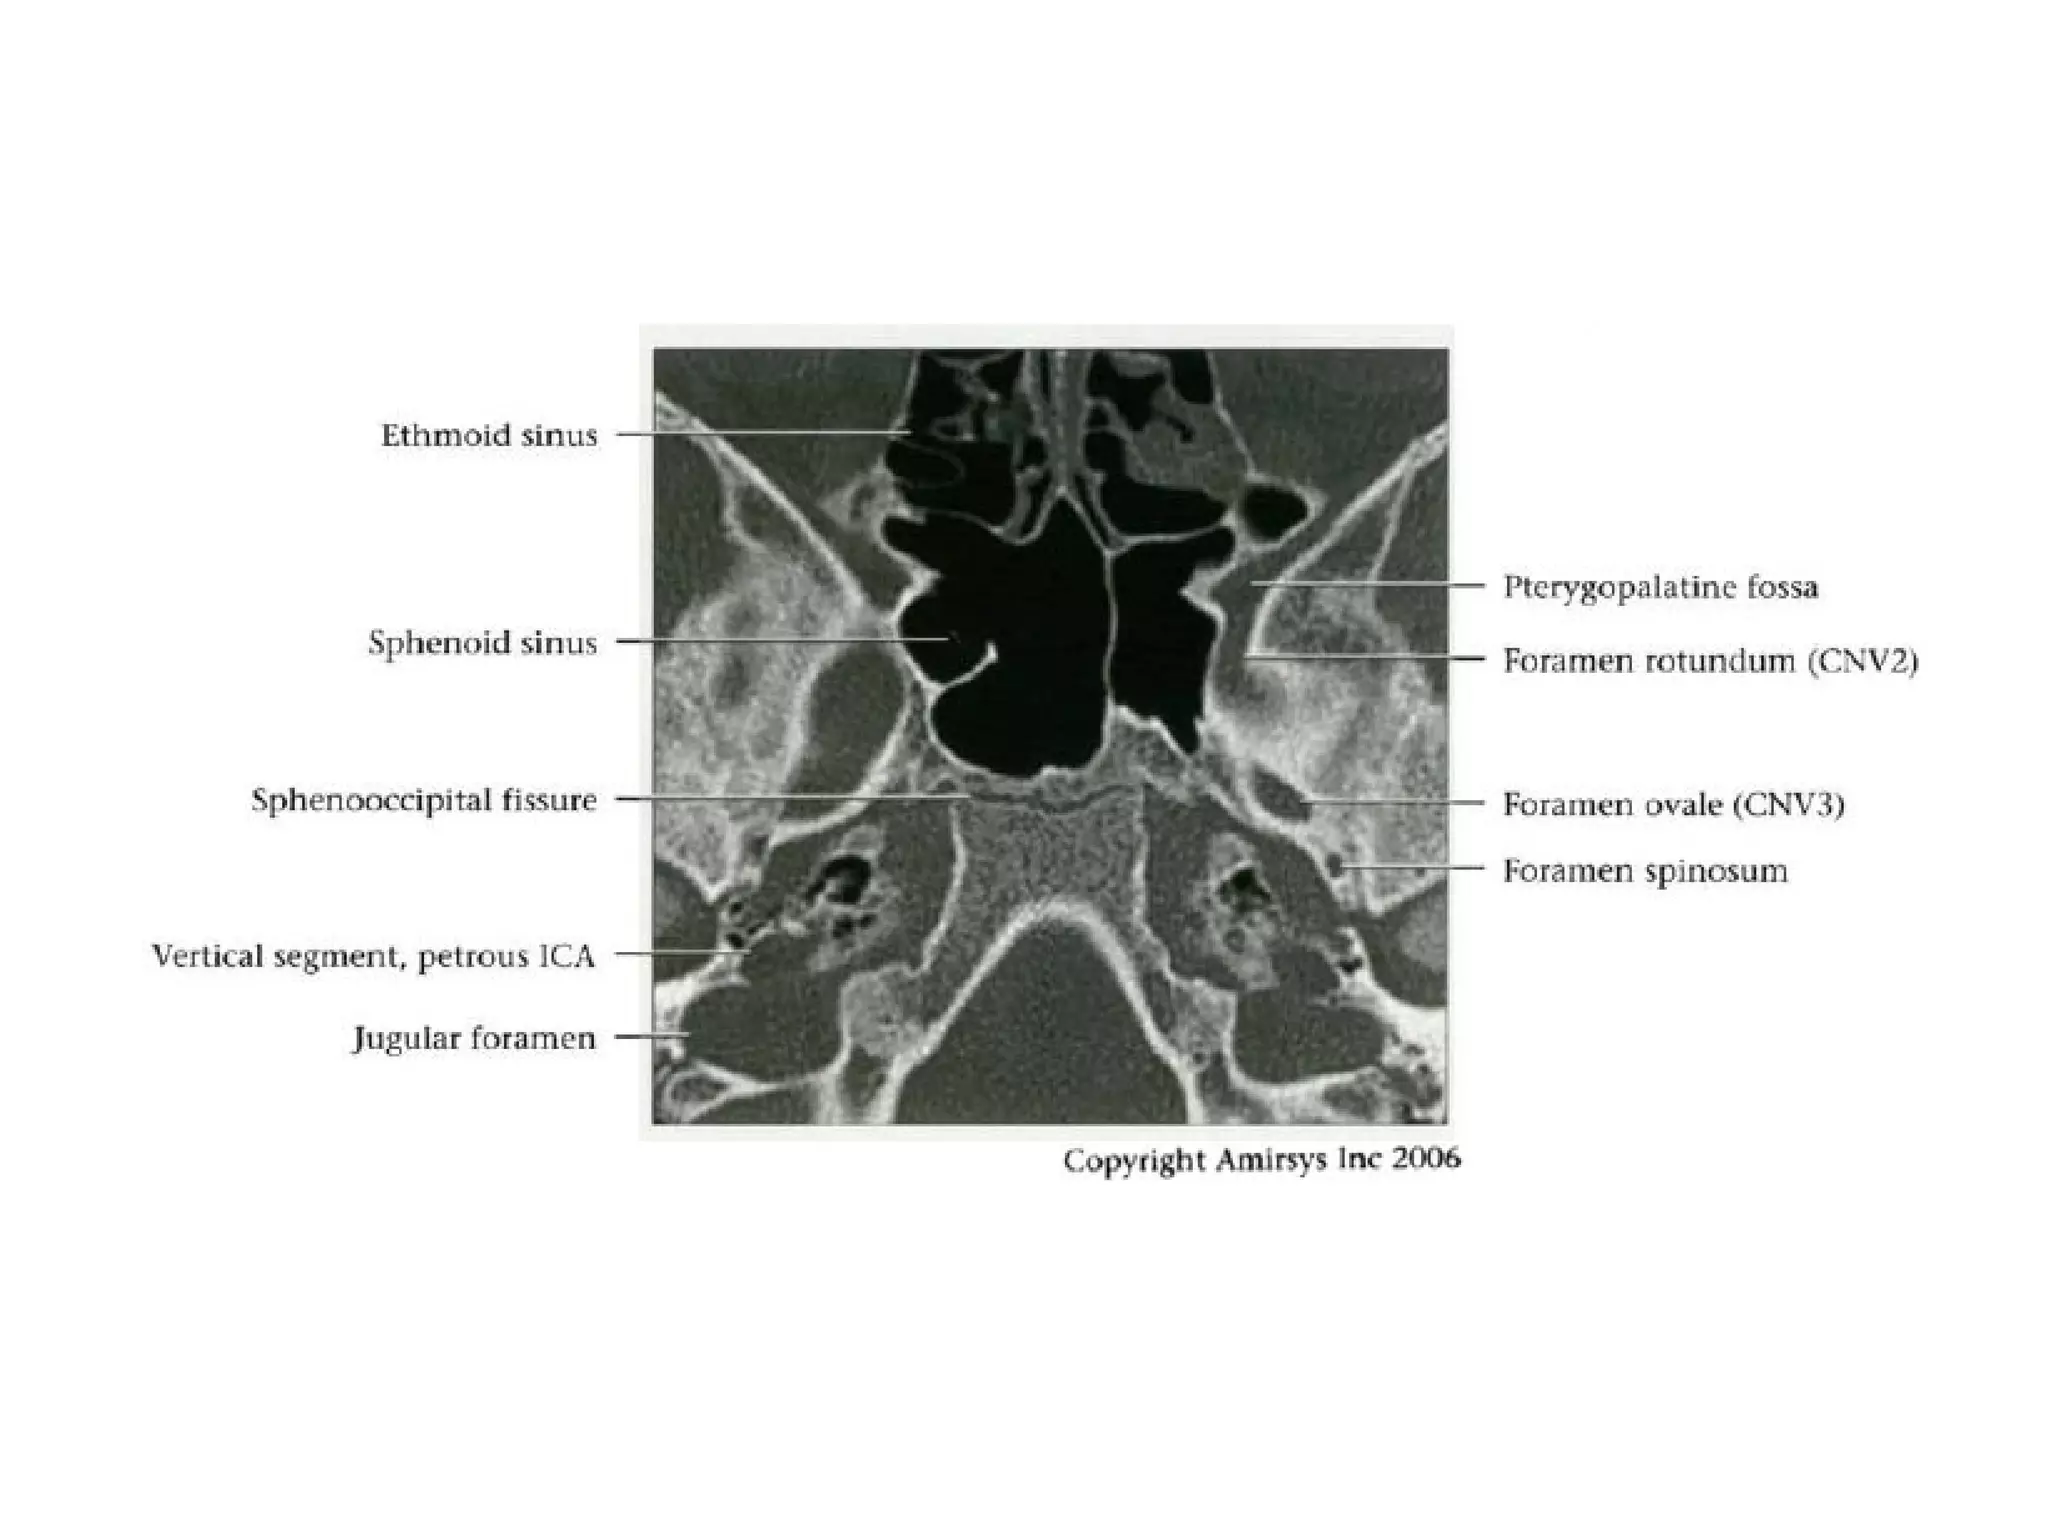

Divisions (Post-Ganglionic) of CNS

Maxillary nerve (CNV2)

• Courses in cavernous sinus lateral wall

below CNV 1

• Exits skull through foramen rotundum

• Traverses roof of pterygopalatine fossa

• Continues as infraorbital nerve in floor of

orbit

• Exits orbit through infraorbital foramen

- Sensory to cheek and upper teeth

Mandibular nerve (CNV3)

• Does not pass through cavernous sinus

• Exits directly from Meckel cave, passing inferiorly

through foramen ovaIe into masticator space

• Carries both motor and sensory fibers

- Motor root bypasses TG, joins V3 as it exits through

foramen ovale

- Divides into masticator (muscles of mastication) and

mylohyoid nerves (mylohyoid and anterior belly of

digastric muscles)

- Masticator nerve take off just below skull base

- Mylohyoid nerve take off at mandibular foramen

• Main sensory branches include inferior alveolar, lingual

and auriculotemporal nerves